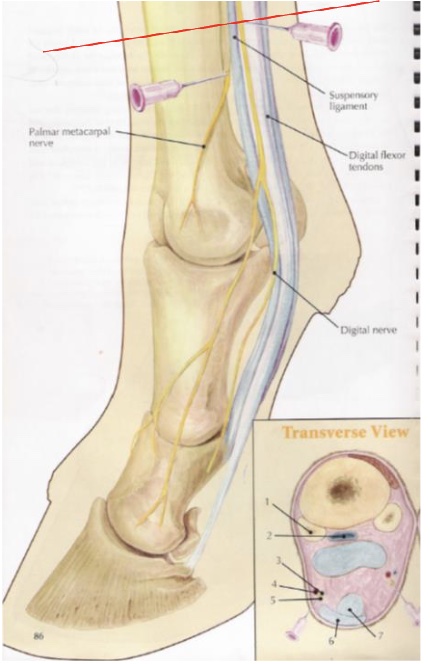

what is desensitized in a low 4 point nerve block (proximal to fetlock)

metocarpo(tarso)phalangeal joint & structures distal

distal aspects of suspensory branches